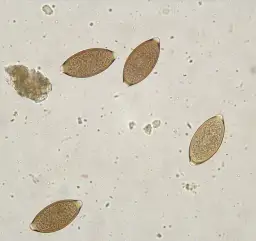

Anaplazmoza u psa to groźna choroba odkleszczowa, wywoływana przez bakterie z rodzaju Anaplasma. Najczęściej spotykane gatunki to Anaplasma phagocytophilum i Anaplasma platys. Te mikroorganizmy atakują białe krwinki i płytki krwi, prowadząc do poważnych zaburzeń w organizmie czworonoga.

Głównym wektorem przenoszącym bakterie Anaplasma są kleszcze. W Polsce najczęściej spotykamy kleszcza pospolitego (Ixodes ricinus), który jest głównym nosicielem tych patogenów. Do zarażenia dochodzi, gdy zakażony kleszcz podczas żerowania wprowadza bakterie do organizmu psa.